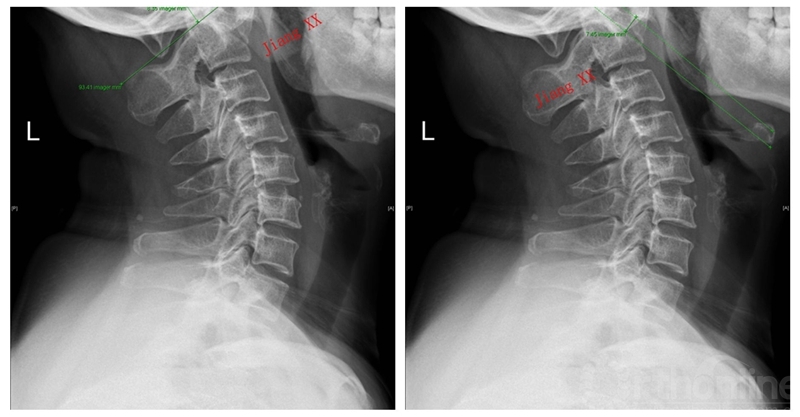

术前X线

下颈椎原来代偿性改变的曲度,无论是过曲还是过伸都得到有效恢复,颈椎的矢状面力线更加平衡。